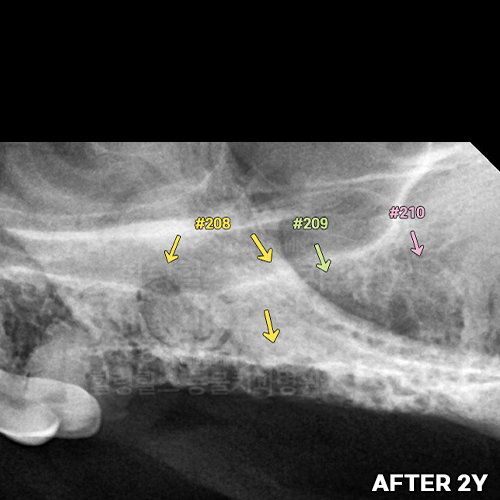

[강아지발치] 잇몸뼈가 녹은 구멍에 자기잇몸뼈가 튼튼하게 재생되어 채워졌어 - 강아지치아발치 2년 후 구강X-ray 비교! -